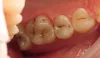

Исходная ситуация.